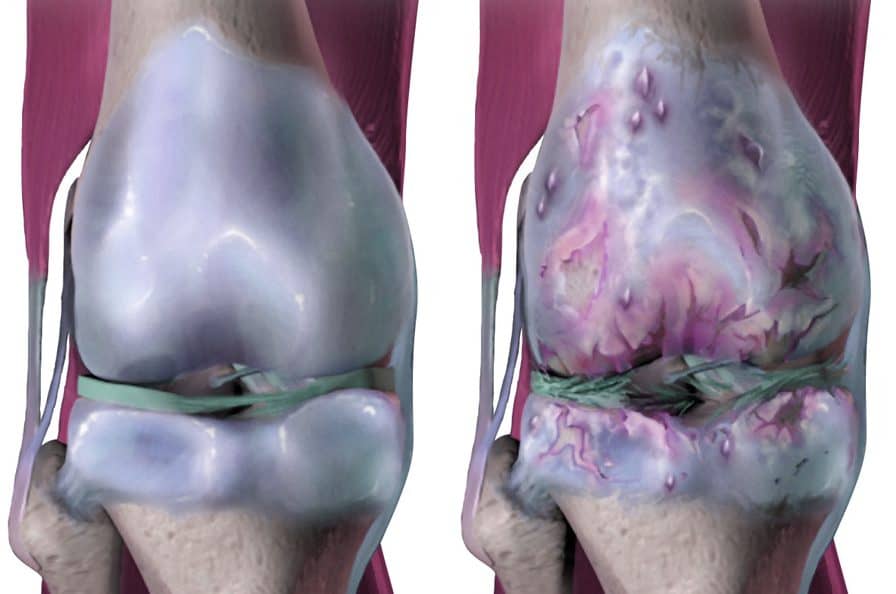

Остеоартритът на коляното е най-честата форма на остеоартрит. Той е резултат от дегенерацията на хрущяла в коляното, която може да се случи, наред с други неща, поради стареене, носене на наднормено тегло и нараняване. Т.е. имаме и биотични причини, което означава, „зелена“ светлина за правилно лечение.

Остеоартритът на коляното се причинява от разграждането на хрущяла, защитната тъкан, която позволява на ставните кости да се плъзгат една върху друга (вижте таблото отново по-горе). В крайна сметка загубата на хрущял може да бъде толкова тежка, че по същество не е останало нищо, което да покрива краищата на костите в колянната става (известно като аномалия кост върху кост). Разхлабените тела в ставното пространство също могат да допринесат за болка и скованост.